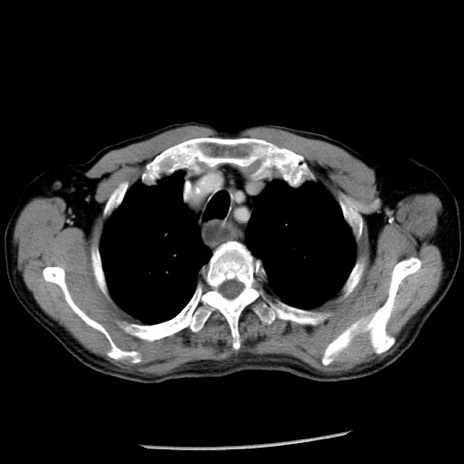

冠状断像